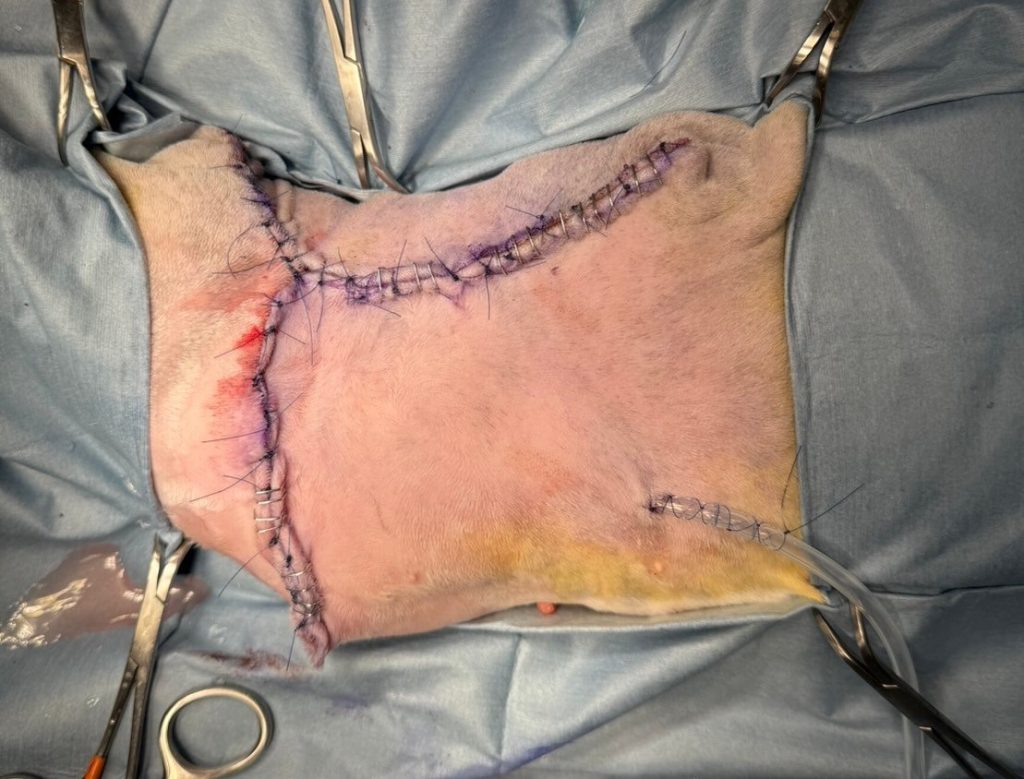

以Y字形(找尋各區域最小張力的關閉法)關閉傷口。

縫合前放置皮下引流管。

最後,將傷口包紮起來,手術結束。

很幸運的,整個手術過程都和術前計畫的差不多,從照片中可見毛孩的出血量是非常少的。

每個預定的步驟,都被我們團隊很順利的執行過去,可以說是一個「沒有驚喜」的手術。